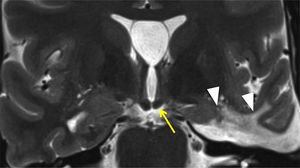

Mujer de 31 años con lesión en el tálamo izquierdo (punta de flecha en A, plano coronal potenciado en T2) con adelgazamiento secundario del fórnix (flecha negra en A) y del cuerpo mamilar ipsolateral (punta de flecha negra en B) respecto al cuerpo mamilar derecho, indicado en punta de flecha blanca en B.